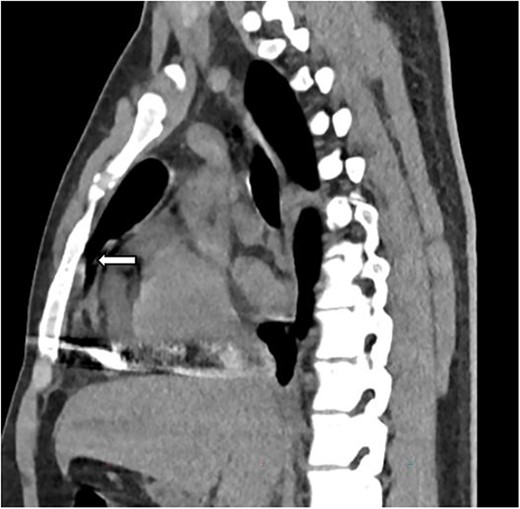

The complete blood count showed white cell count of 4300 cells, hemoglobin of 18.7 g/dl, and platelet of 285 000. Serum electrolyte, albumin and liver function tests were within normal range and creatinine was 1.19 mg/dl. Chest X ray showed bullet left of the sternum within the inferior aspect of the cardiac silhouette. Contrast CT scan detected minimal bilateral pleural collection with right basal segment atelectasis with 2.3 × 1.1 cm metallic density foreign body in the mediastinum located over the inferior border of ventricular wall (Figs 1–3). Troponin was 432.4 ng/ml. Electrocardiography showed V2 lead ST segment elevation. All the other leads were normal. The patient had three echocardiographs done, and only one showed the presence of foreign body within the myocardium of the left ventricle. Otherwise, no wall motion abnormality, or any sign of heart failure was detected.

Sagittal image depicting foreign body within the myocardium (white arrow).